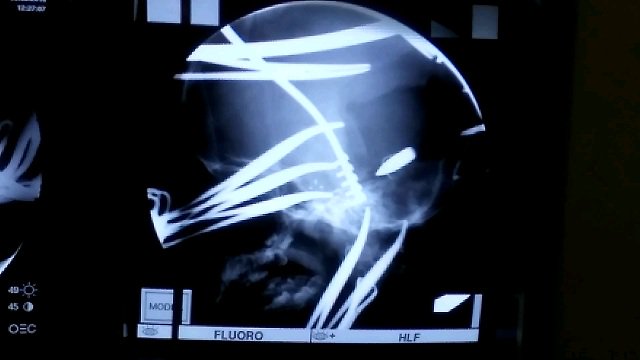

وأوضح أنه "بعد إجراء الفحوصات السريرية والإشعاعية تبين أن الرصاصة اخترقت عمق الدماغ ماتسببت له بشلل".

وتابع أنه تم "إجراء عملية معقدة لإخراج الرصاصة وتكللت بالنجاح"، مشيرا إلى أن "العملية أجريت بمساعدة فريق طبي مكون من د. مكرم نور الدين و د. اوفى اكثم و اخصائي التخدير د. احمد علي محروس ومساعد مخدر علاء حسين والممرضة فردوس ناظم والفيزياوي احمد علي".